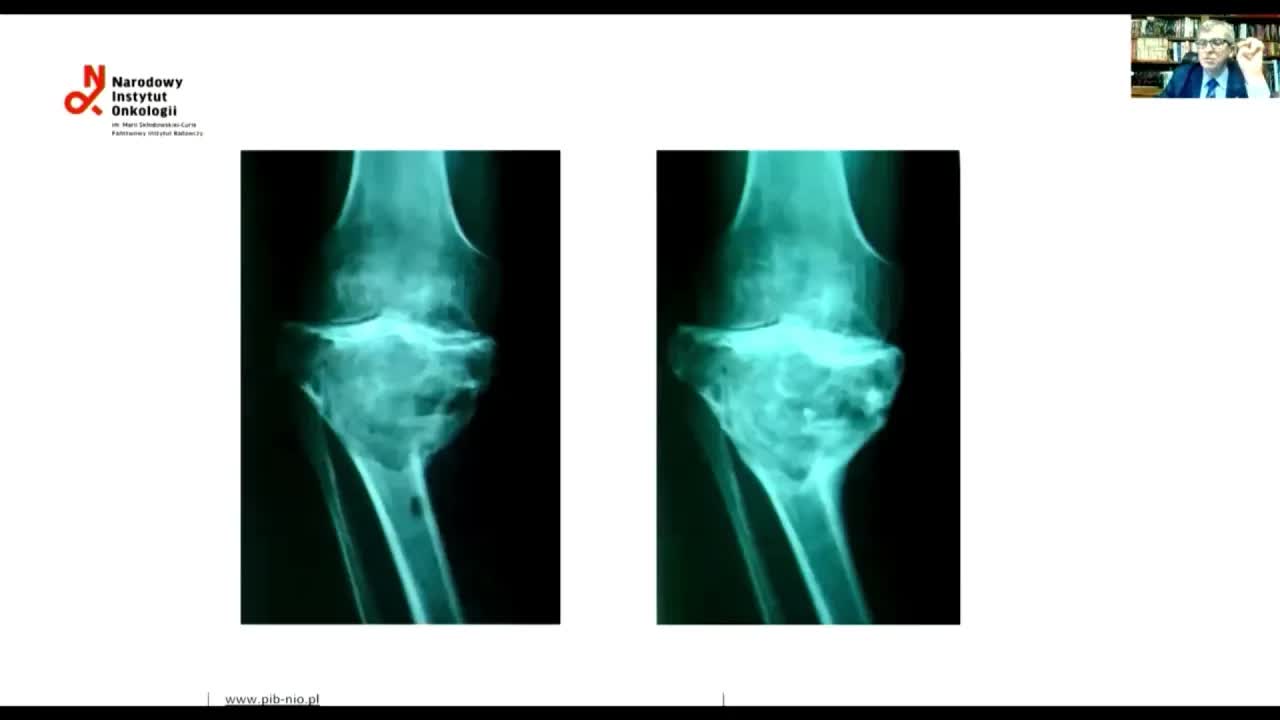

Гигантоклеточная опухоль длинных трубчатых костей: эндопротезировать нельзя, экскохлеацию!

Бадыров Роми Надырович

Гигантоклеточная опухоль длинных трубчатых костей: эндопротезировать, нельзя экскохлеацию!

Соколовский Анатолий Владимирович

Оценка эффективности терапии деносумабом гигантоклеточной опухоли кости по данным лучевых методов

Федорова Александра Владимировна

Результаты одноцентрового исследования эффективности деносумаба при гигантоклеточной опухоли кости

Тарарыкова Анастасия Алексеевна

Деносумаб в лечении гигантоклеточной опухоли кости (Giant cell tumor and Denosumab)

Piotr Rutkowski (Петр Рутковский)